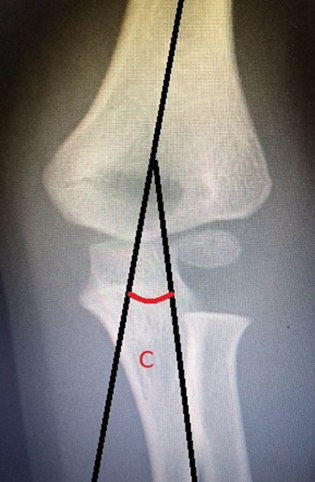

Otro ángulo importante es el de carga del codo, que puede ser evaluado en radiografía AP, o clínicamente. Está formado por la intersección de la línea del eje medio del brazo con la línea del eje medio del antebrazo (Figura 7). Sirve para medir el alineamiento coronal del brazo con el antebrazo y determina la desviación en varo o en valgo de la extremidad. Su valor varía entre 5% y 15° en el 95% de la población, con un promedio de 10°24,25.